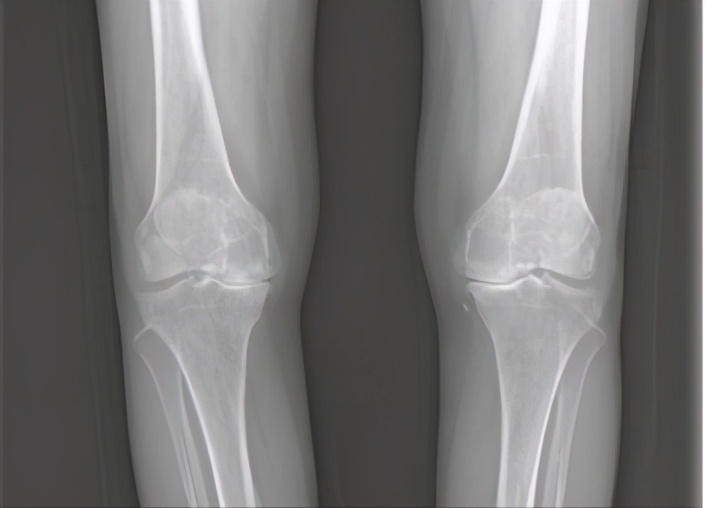

骨关节炎

60岁以上的人群4号位疼痛最常见的原因是膝关节骨关节炎,体重大的人更容易出现这个位置的疼痛。主要是由于各种原因导致长时间的内侧关节间隙受压磨损,软骨磨损了之后出现软骨炎,从而引发疼痛,还可能会出现关节的变形、O型腿等。